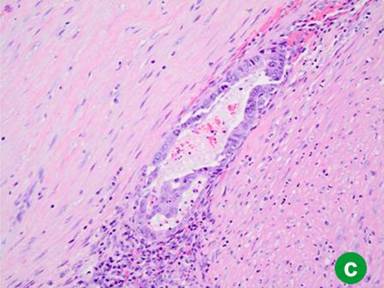

In 2011, four years after her original presentation, we performed a classic Whipple operation with a blood loss of 550 mL. Intraoperative frozen section of the common bile duct was negative for malignancy. The postoperative course was unremarkable and the patient was discharged to home 8 days later. Pathology report showed intraductal oncocytic papillary carcinoma 9 cm in greatest diameter, with 25 negative lymph nodes and microscopically negative surgical margins. The tumor showed diffuse high grade dysplasia and architectural complexity as well as mucin-containing intraepithelial lumina (Figure 2ab). The invasive component of the tumor was confined to the pancreas, moderately differentiated, measuring 1.9 cm in greatest diameter (Figure 2c). Additionally, a somatic KRAS mutation was identified at codon 12 and consisted of c.34G>A mutation. The case was discussed at Tumor Board and patient received adjuvant gemcitabine for six months. PET scan performed 16 months after Whipple operation showed no evidence of recurrent disease.

Figure 2. a. Low power image (20x) illustrates intraductal papillary growth pattern with oncocytic cells arranged in complex arborizing papillae. b. High power image (40x) showing distinctive mucin-containing intraepithelial lumina, imparting a cribriform architecture. c. Low power image (20x) displaying an invasive gland adjacent to the intraductal oncocytic papillary neoplasm. |